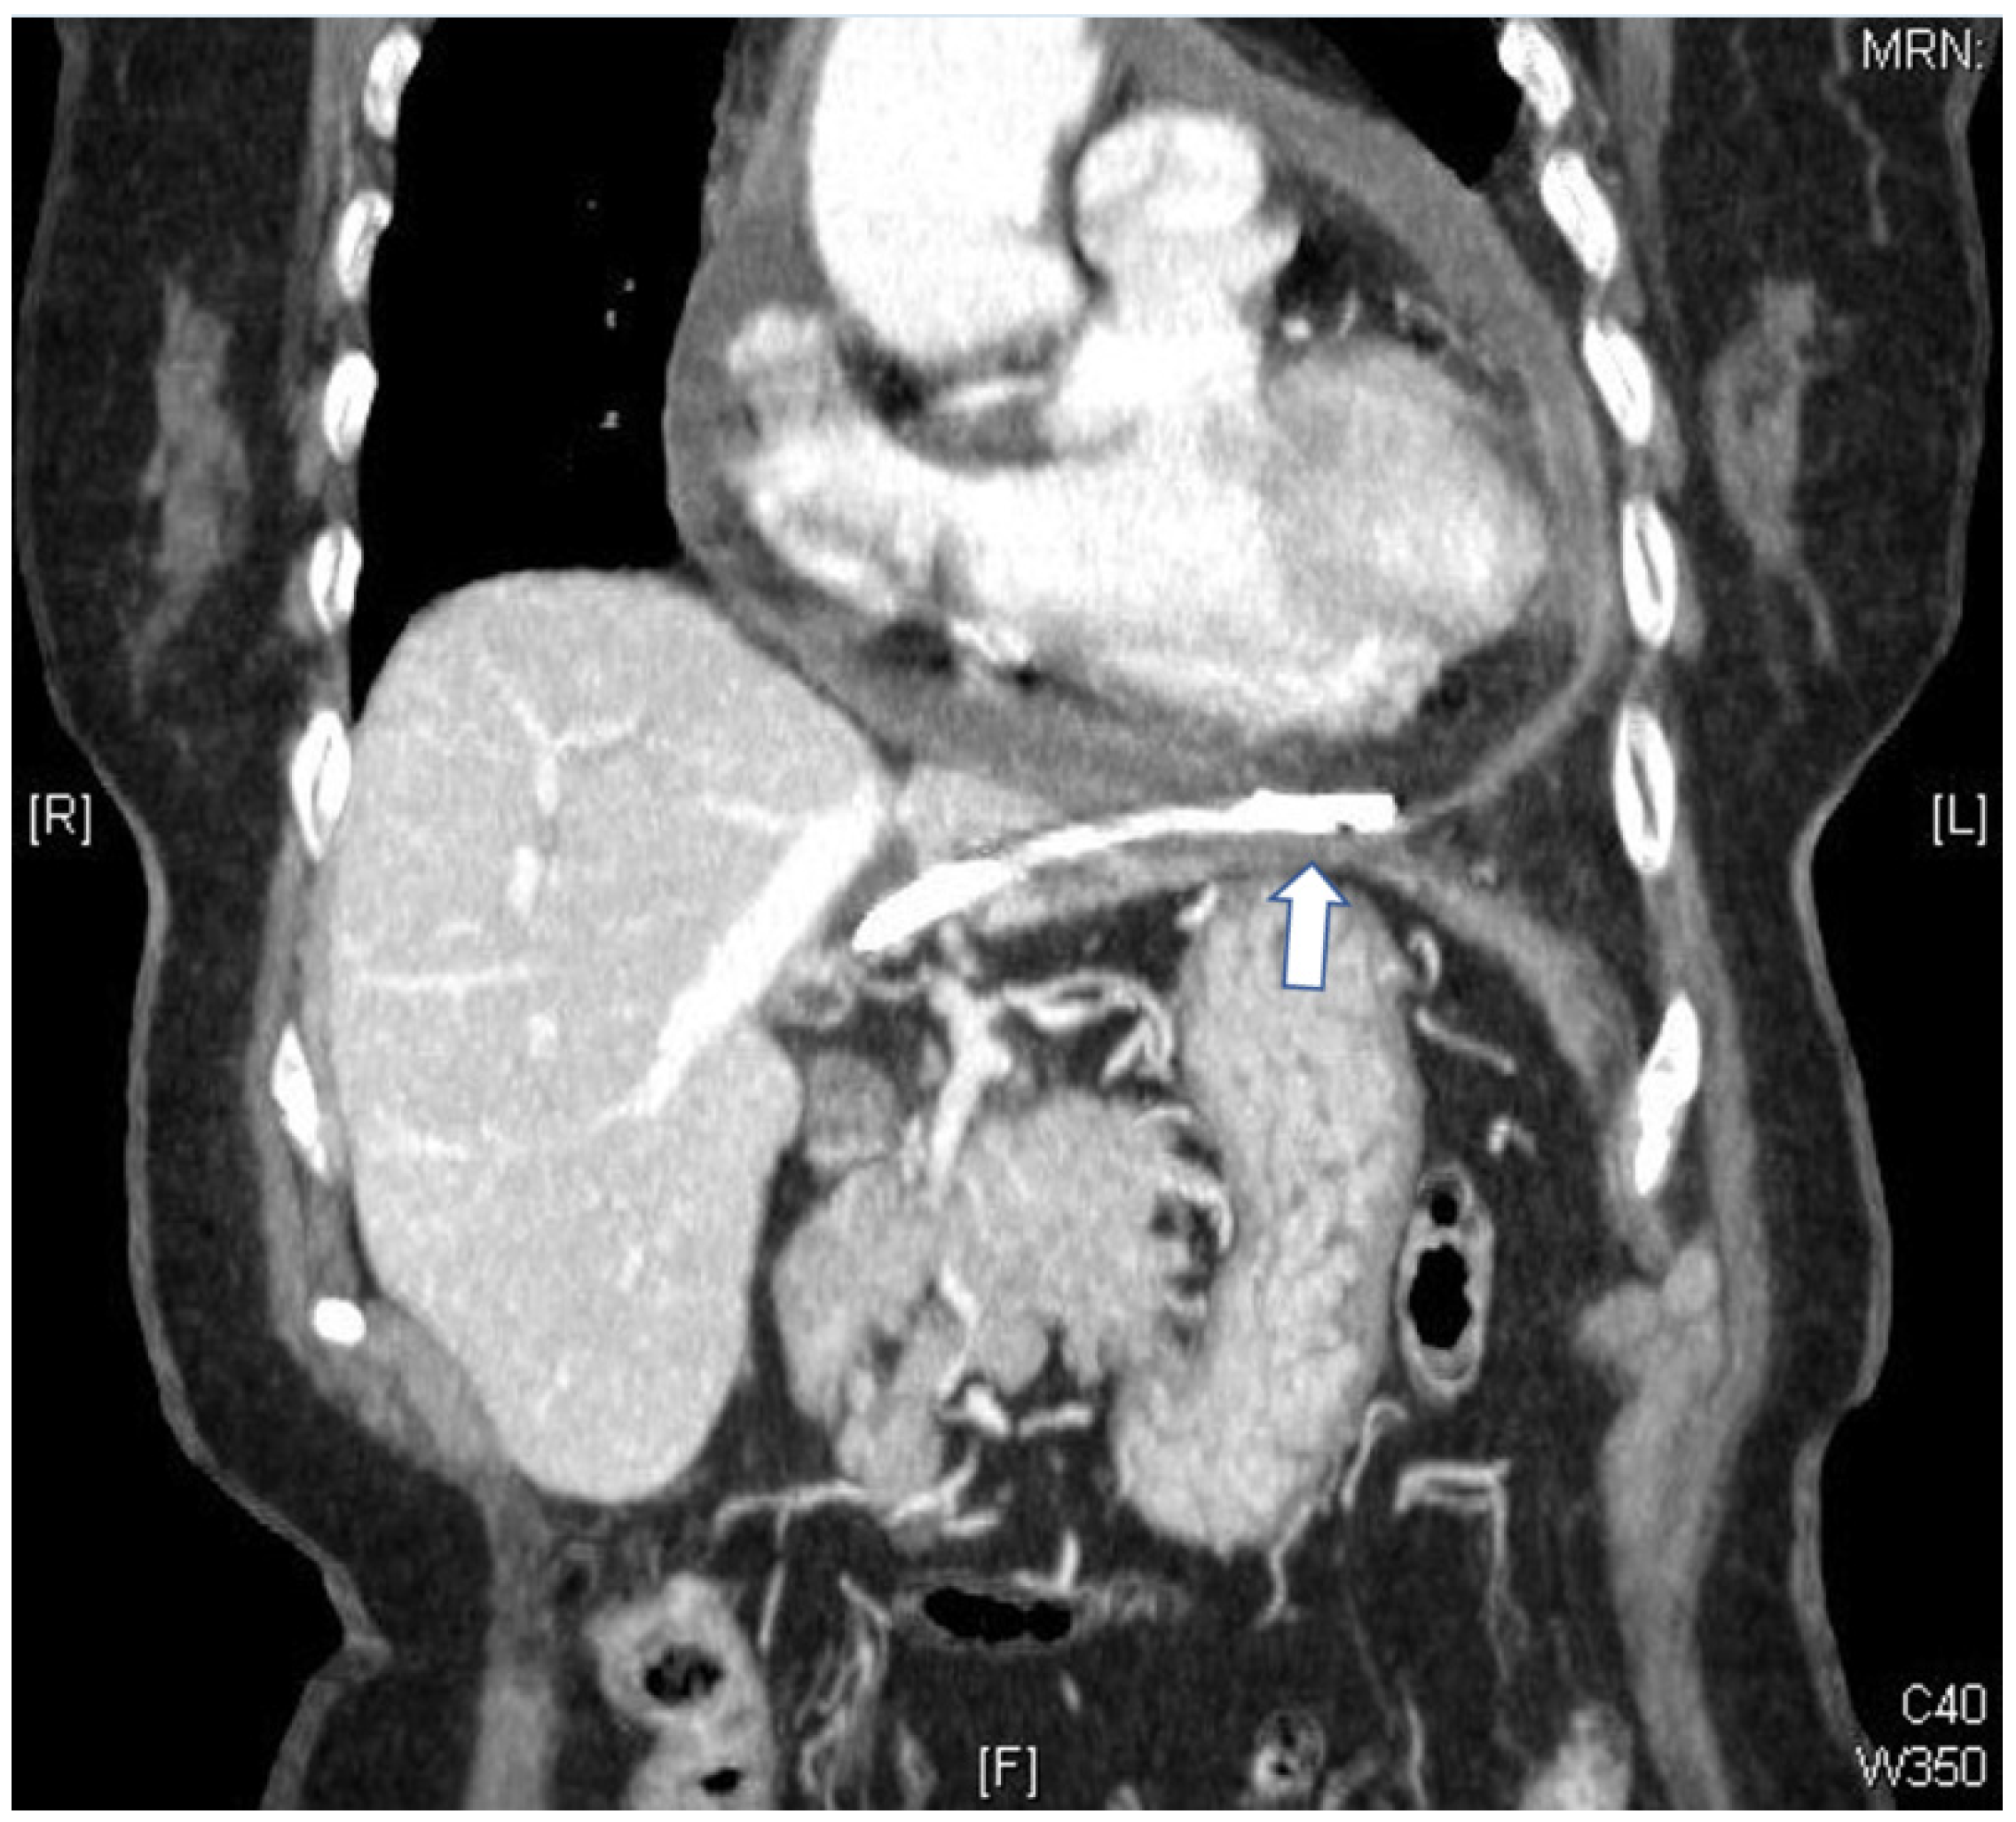

Bacterial Pericarditis Caused by Penetration of a Migrated Biliary Stent from the Lateral Segment of the Liver: A Case Report